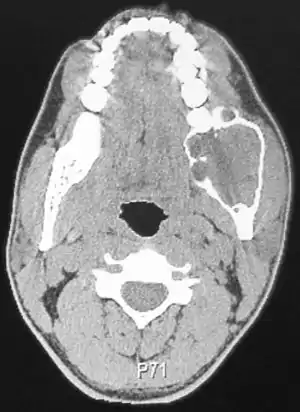

Для діагностики стану тканини, у медицині використовують гістологічні, цитологічні та рентгенологічні дослідження. Основним методом лікування пухлин залишається хірургічний, який у ряді випадків поєднується з призначенням хіміопрепаратів, гормональних засобів та променевою (рентгенівською або радіоізотопною) терапією.